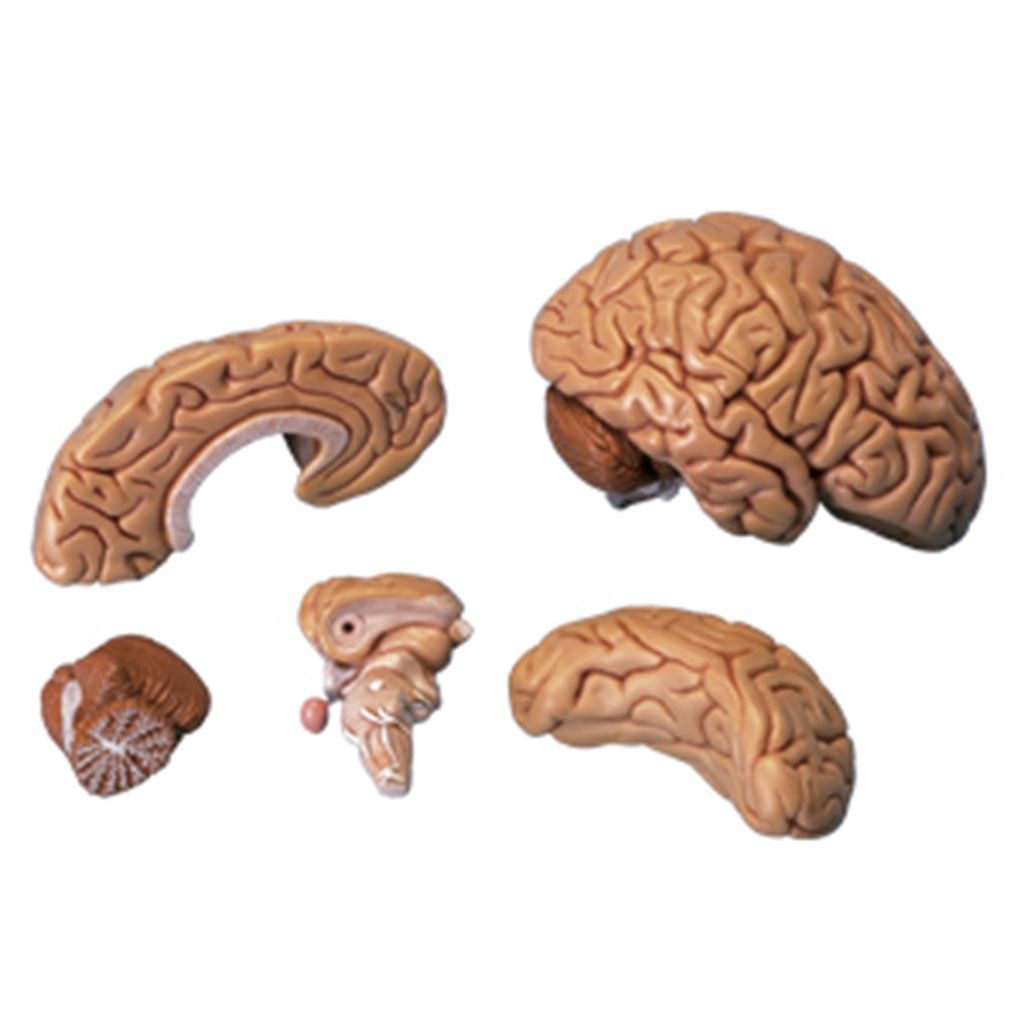

CEREBRO ROSA CON ARTERIAS

CEREBRO ROSA CON ARTERIAS

$1,658.80

CEREBRO ROSA CON ARTERIAS

CEREBRO ROSA CON ARTERIAS